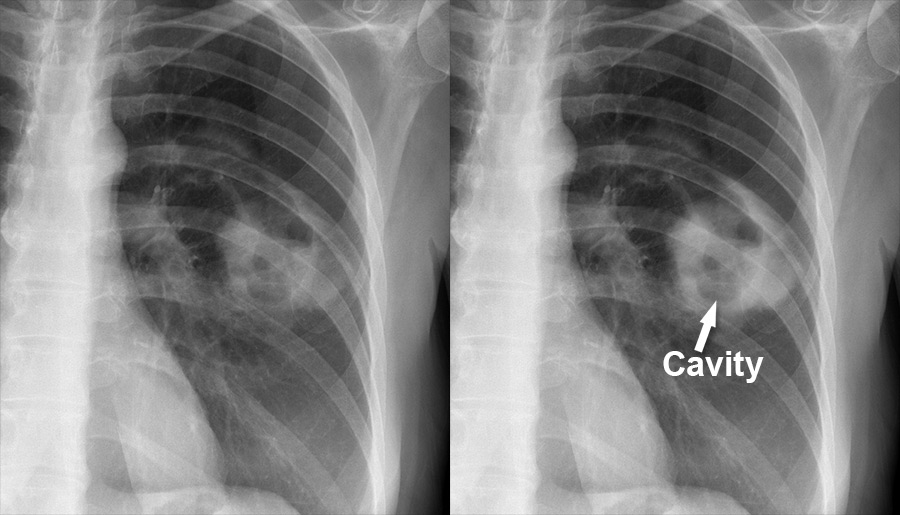

54. 一位75歲女性糖尿病患,本次因發燒、咳黃痰住院,診斷為社區性肺炎,胸部X光片如下圖,下列何者是箭頭所指的變化?

(A) 肺空洞

肺空洞:黑色肺癌:圓形肺塌陷:氣管會偏移...

肺空洞: